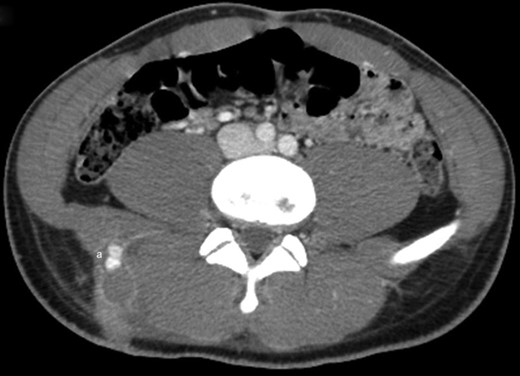

Examination on admission revealed an actively bleeding 2-cm wide stab wound in the right lumbar paraspinal region. A contrast-enhanced CT of the pelvis showed an enhancing lesion consistent with a pseudoaneurysm extending from a branch of a right lumbar artery (Figs 1 and 2). The patient was transferred to the interventional radiology suite where angiography confirmed the diagnosis (Fig. 3). The pseudoaneurysm was then successfully embolized using platinum microcoils (Fig. 4), which were positioned in the lumbar artery, proximal and distal to the origin of the pseudoaneurysm. The patient tolerated the procedure well and was discharged the following day without any further complication.

Axial cut from the same contrast-enhanced CT scan of the lower abdomen and pelvis showing a 1.6-cm bilobed, enhancing lesion, consistent with pseudoaneurysm, presumably extending from a branch of a right lumbar artery (a).